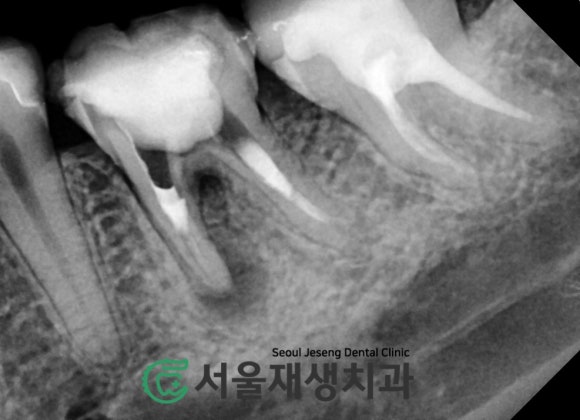

주기적인 뿌리 청소와 소독으로

치근단염증이 줄어드는 중입니다.

=뼈가 재생되는 중입니다!

시간이 지날수록

뿌리 끝에 달려있던

까만 주머니의 크기가

감소합니다!

염증 주머니가 작아지는 것은

골조직의 재생을 의미합니다^^